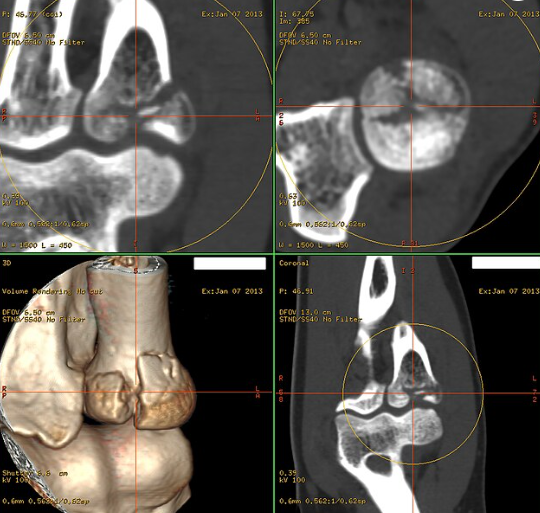

정확한 평가가 필요한 경우 CT나 MRI 검사로 골절 상태와 주변 인대, 힘줄 손상 여부를 확인합니다.

신경 및 혈관 손상 여부도 검사하는 것이 중요합니다.